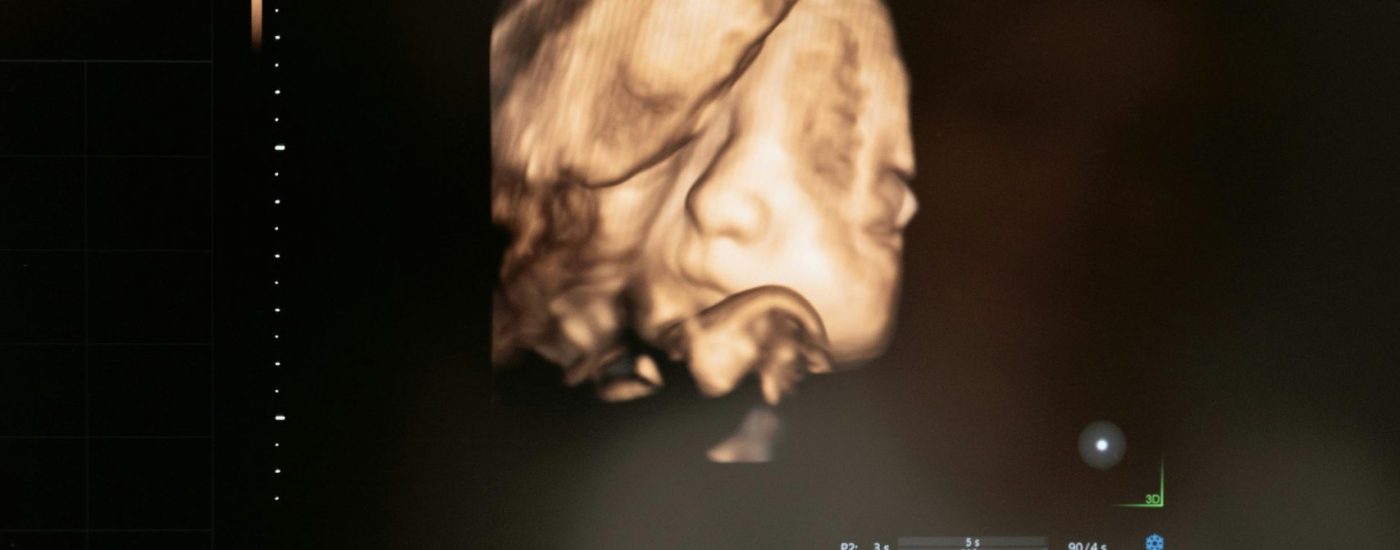

Descubre la magia de ver por primera vez a tu bebé en un entorno emotivo creado por nuestro equipo de Matronas. Equipados con la última tecnología en ecografía 5D y 6D, capturamos imágenes tridimensionales en movimiento y tiempo real.

Durante la sesión, los padres y familiares disfrutan de la imagen en vivo en una gran pantalla, mostrando detalles como el sexo, movimientos y la cara perfectamente formada del bebé. Esta experiencia, guiada por nuestras matronas especializadas, es emocional, no diagnóstica, brindando momentos inolvidables y la oportunidad de resolver todas tus dudas.

Disfruta de los gestos y movimientos de tu bebé

Observa las facciones bien definidas de tu bebé. Detalla cómo se toca la cara, sonríe, bosteza y chupa un dedo. Incluye biometría fetal, peso estimado, posición y latido fetal.